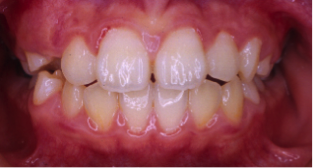

過蓋咬合(かがいこうごう)※ 非抜歯

20歳/女性

悩み:噛み合わせが深い

下の前歯が上の歯茎に食い込んでいる状態

治療期間:約2年

治療前

治療後

深い噛み合せを改善する治療が必要になりました。

先に深い噛み合せを上げないと矯正装置がつかないので、噛み合せの深さを改善する治療から行なう矯正治療となりました。